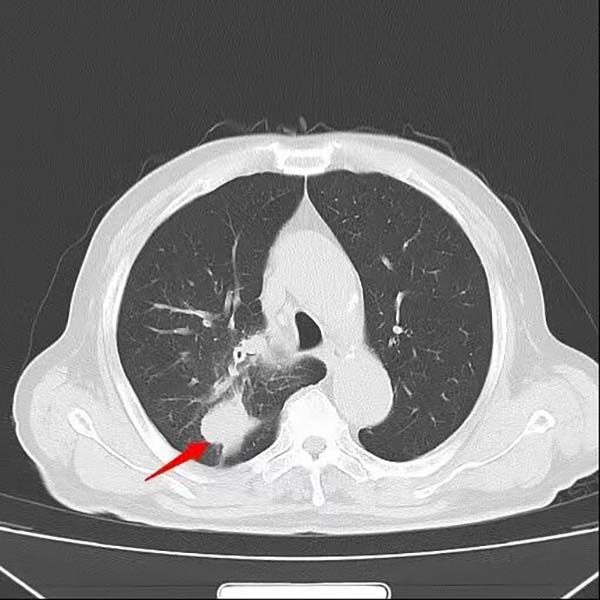

经过一个周期的治疗后,患者喘憋、咳嗽等呼吸道症状明显缓解,复查影像显示右肺上叶肿物显著缩小,疗效评估良好。这一结果让患者及家属重拾治疗信心,也为下一阶段治疗奠定了基础。